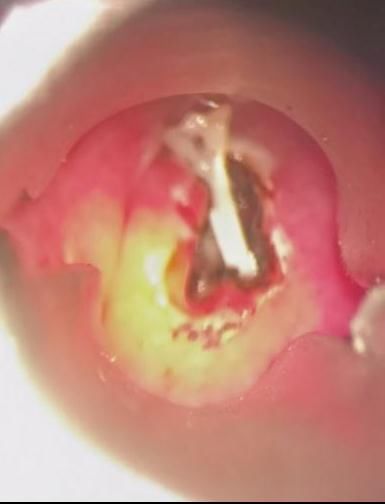

【 鱼刺卡喉|鱼刺卡喉用“老土方”?专家:不科学且危险!】经过详细检查,哈医大四院耳鼻咽喉头颈外科主任周彬为王先生进行急诊全麻下支撑喉镜下下咽后壁切开异物取出术。术中可见咽后壁粘膜光滑,会厌高度偏左侧的咽后壁略隆起。在隆起处以激光纵行切开粘膜及粘膜下组织,脓性液体流出,其内可见一白色鱼刺。完整取出鱼刺,可见其上端呈针尖状,整体呈弧形,边缘锐利光滑,无破损。术后,王先生恢复良好。